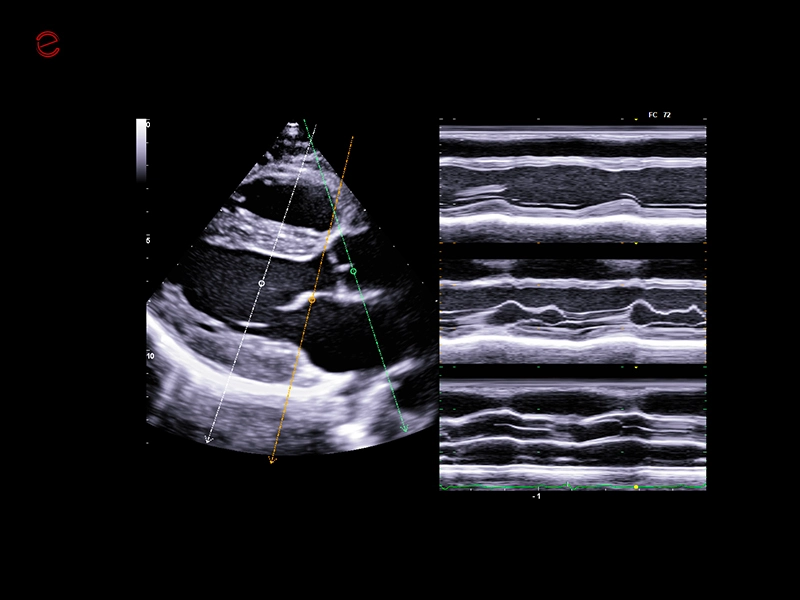

IDEAL FOR A VARIETY OF CLINICAL APPLICATIONS

High-quality imaging on-the-go

A compact and dependable partner, the MyLab™C25 is designed to support your daily practice with ease, providing high-quality imaging for confident diagnostics every time. With MyLab™C25 and its wide range of probes, we provide you with the ability to perform examinations in a broad variety of clinical applications such as general imaging, superficial scanning, cardiology, vascular, gynecology and obstetrics